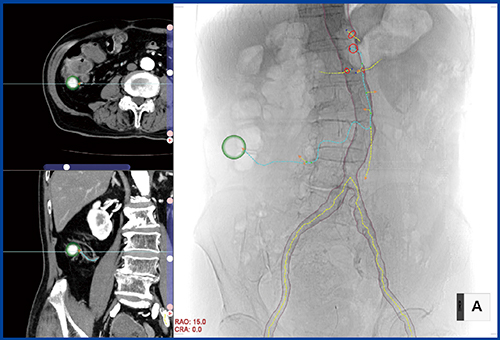

血管IVRモードでは,CTデータを読み込むことで仮想透視画像の作成から主要血管の抽出までが自動で行われる。ターゲット(緑の○)を指定することで,そこに至るルート(血管)を自動抽出し複数(最大3本)表示されるため(水色,黄色),IVRの際の最適なルートを事前に確認できる。さらに,主要な血管の分岐部にはマーカーが表示され,画像を回転させることでカテーテルの挿入角度を確認でき,術中の手技をサポートする。

このPPPを含めIVRの術前計画の作成を自動化したのが,Ziostation2のアプリケーションとしてリリースされたIVRプランニングだ。IVRプランニングでは,“血管IVRモード”と“非血管IVRモード”でカテーテル術前のプランニングをサポートする。血管IVRモードでは,造影CTのデータを読み込むと仮想透視画像の作成,大動脈や腸骨動脈の輪郭の自動抽出までが行われる。抽出した血管走行や分岐をサーフェスレンダリング表示し,Ray Sum画像と重ね合わせて表示する。出血や腫瘍などのターゲットを指定すると,ターゲットまでのルート(血管)が自動抽出される。最大3本まで候補が提示され,ルートごとに色や名前をつけ,治療を行う血管を鑑別できる。また,分岐血管の方向が表示され,カテーテルの回転方向も確認できるほか,アングルのシミュレーションをリアルタイムに行うことも可能だ。